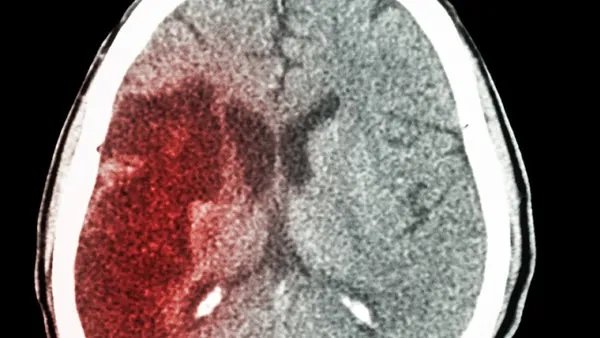

脑出血偏瘫能恢复吗脑出血偏瘫可以恢复。如果病情相对较轻,也可以选择保守治疗来有效控制病情,因为脑出血后很可能形成颅内高压。如果颅内高压得不到有效控制,很可能导致死亡。因此,应该尽最大努力挽救生命。挽救生命的最佳方法是选择保守治疗,然而,如果情况严重,可能也有必要选择手术治疗。